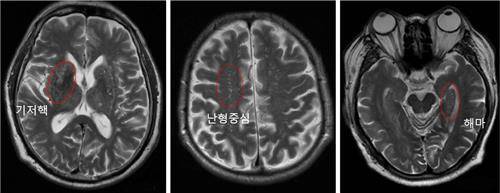

연구팀은 세브란스병원에서 양전자방출단층촬영(PET) 검사로 아밀로이드-베타 단백질 침착(침착이 있으면 알츠하이머병으로 진단함)이 확인된 208명의 알츠하이머병 환자에서 알츠하이머병 진단 시 시행한 3T(Teslaㆍ자장 세기) MRI 뇌 영상 가운데 기저 핵(basal ganglia), 난형 중심(centrum semiovale), 해마(hippocampus) 등 세 부위를 분석해 뇌혈관 주위 공간 확장의 정도를 확인했다.